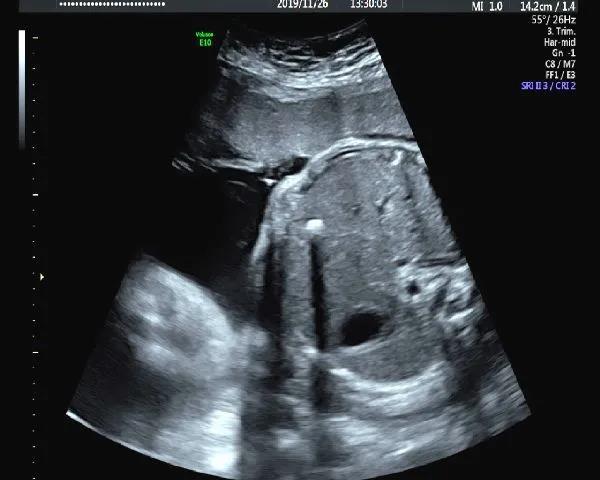

5.肝脏强回声

肝脏的强回声较为少见,可位于肝表面、肝实质内或肝内血管内。位于肝表面的强回声常与胎粪性腹膜炎有关。肝实质内的强回声与缺血坏死、出血、感染等有关,而肝血管内强回声可能与肝内静脉或脐静脉内血栓形成有关。还有就是肝脏的肿瘤可能也存在瘤体内的强回声。

出现肝内强回声时需要排除是否其他器官存在强回声,单纯的肝内强回声出生后可自行消失,除外染色体异常、感染等因素,往往预后良好。